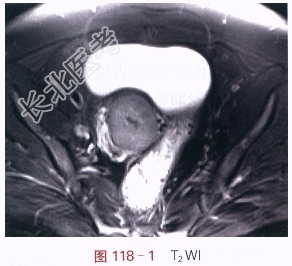

影像学资料如图118-1~图118-4所示。

读片分析:宫颈见内生型肿块,自宫颈外口向颈管内生长,侵犯宫颈深部组织,宫旁组织未受累,T₁WI呈等信号,T₂WI稍高信号,信号较均匀;增强后,瘤体强化较明显、欠均匀,但低于邻近正常的子宫。